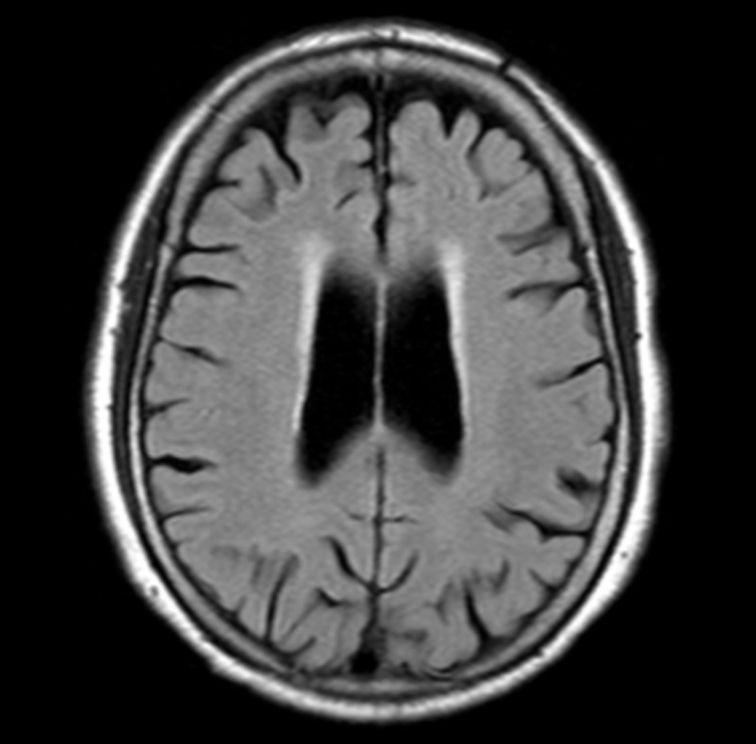

白質高信号領域の体積を自動計測

- 白質高信号領域の体積変化は様々な疾患の兆候になり得る

- 白質高信号領域(脳室周辺白質高信号領域・深部皮質下白質高信号領域)の体積の自動計測